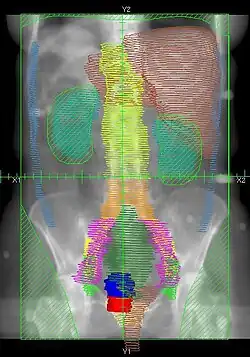

|

Example of a PA whole abdomen/pelvis radiation therapy treatment field used at Tufts/Brown residency program. Actual patient contours should guide field design.

|